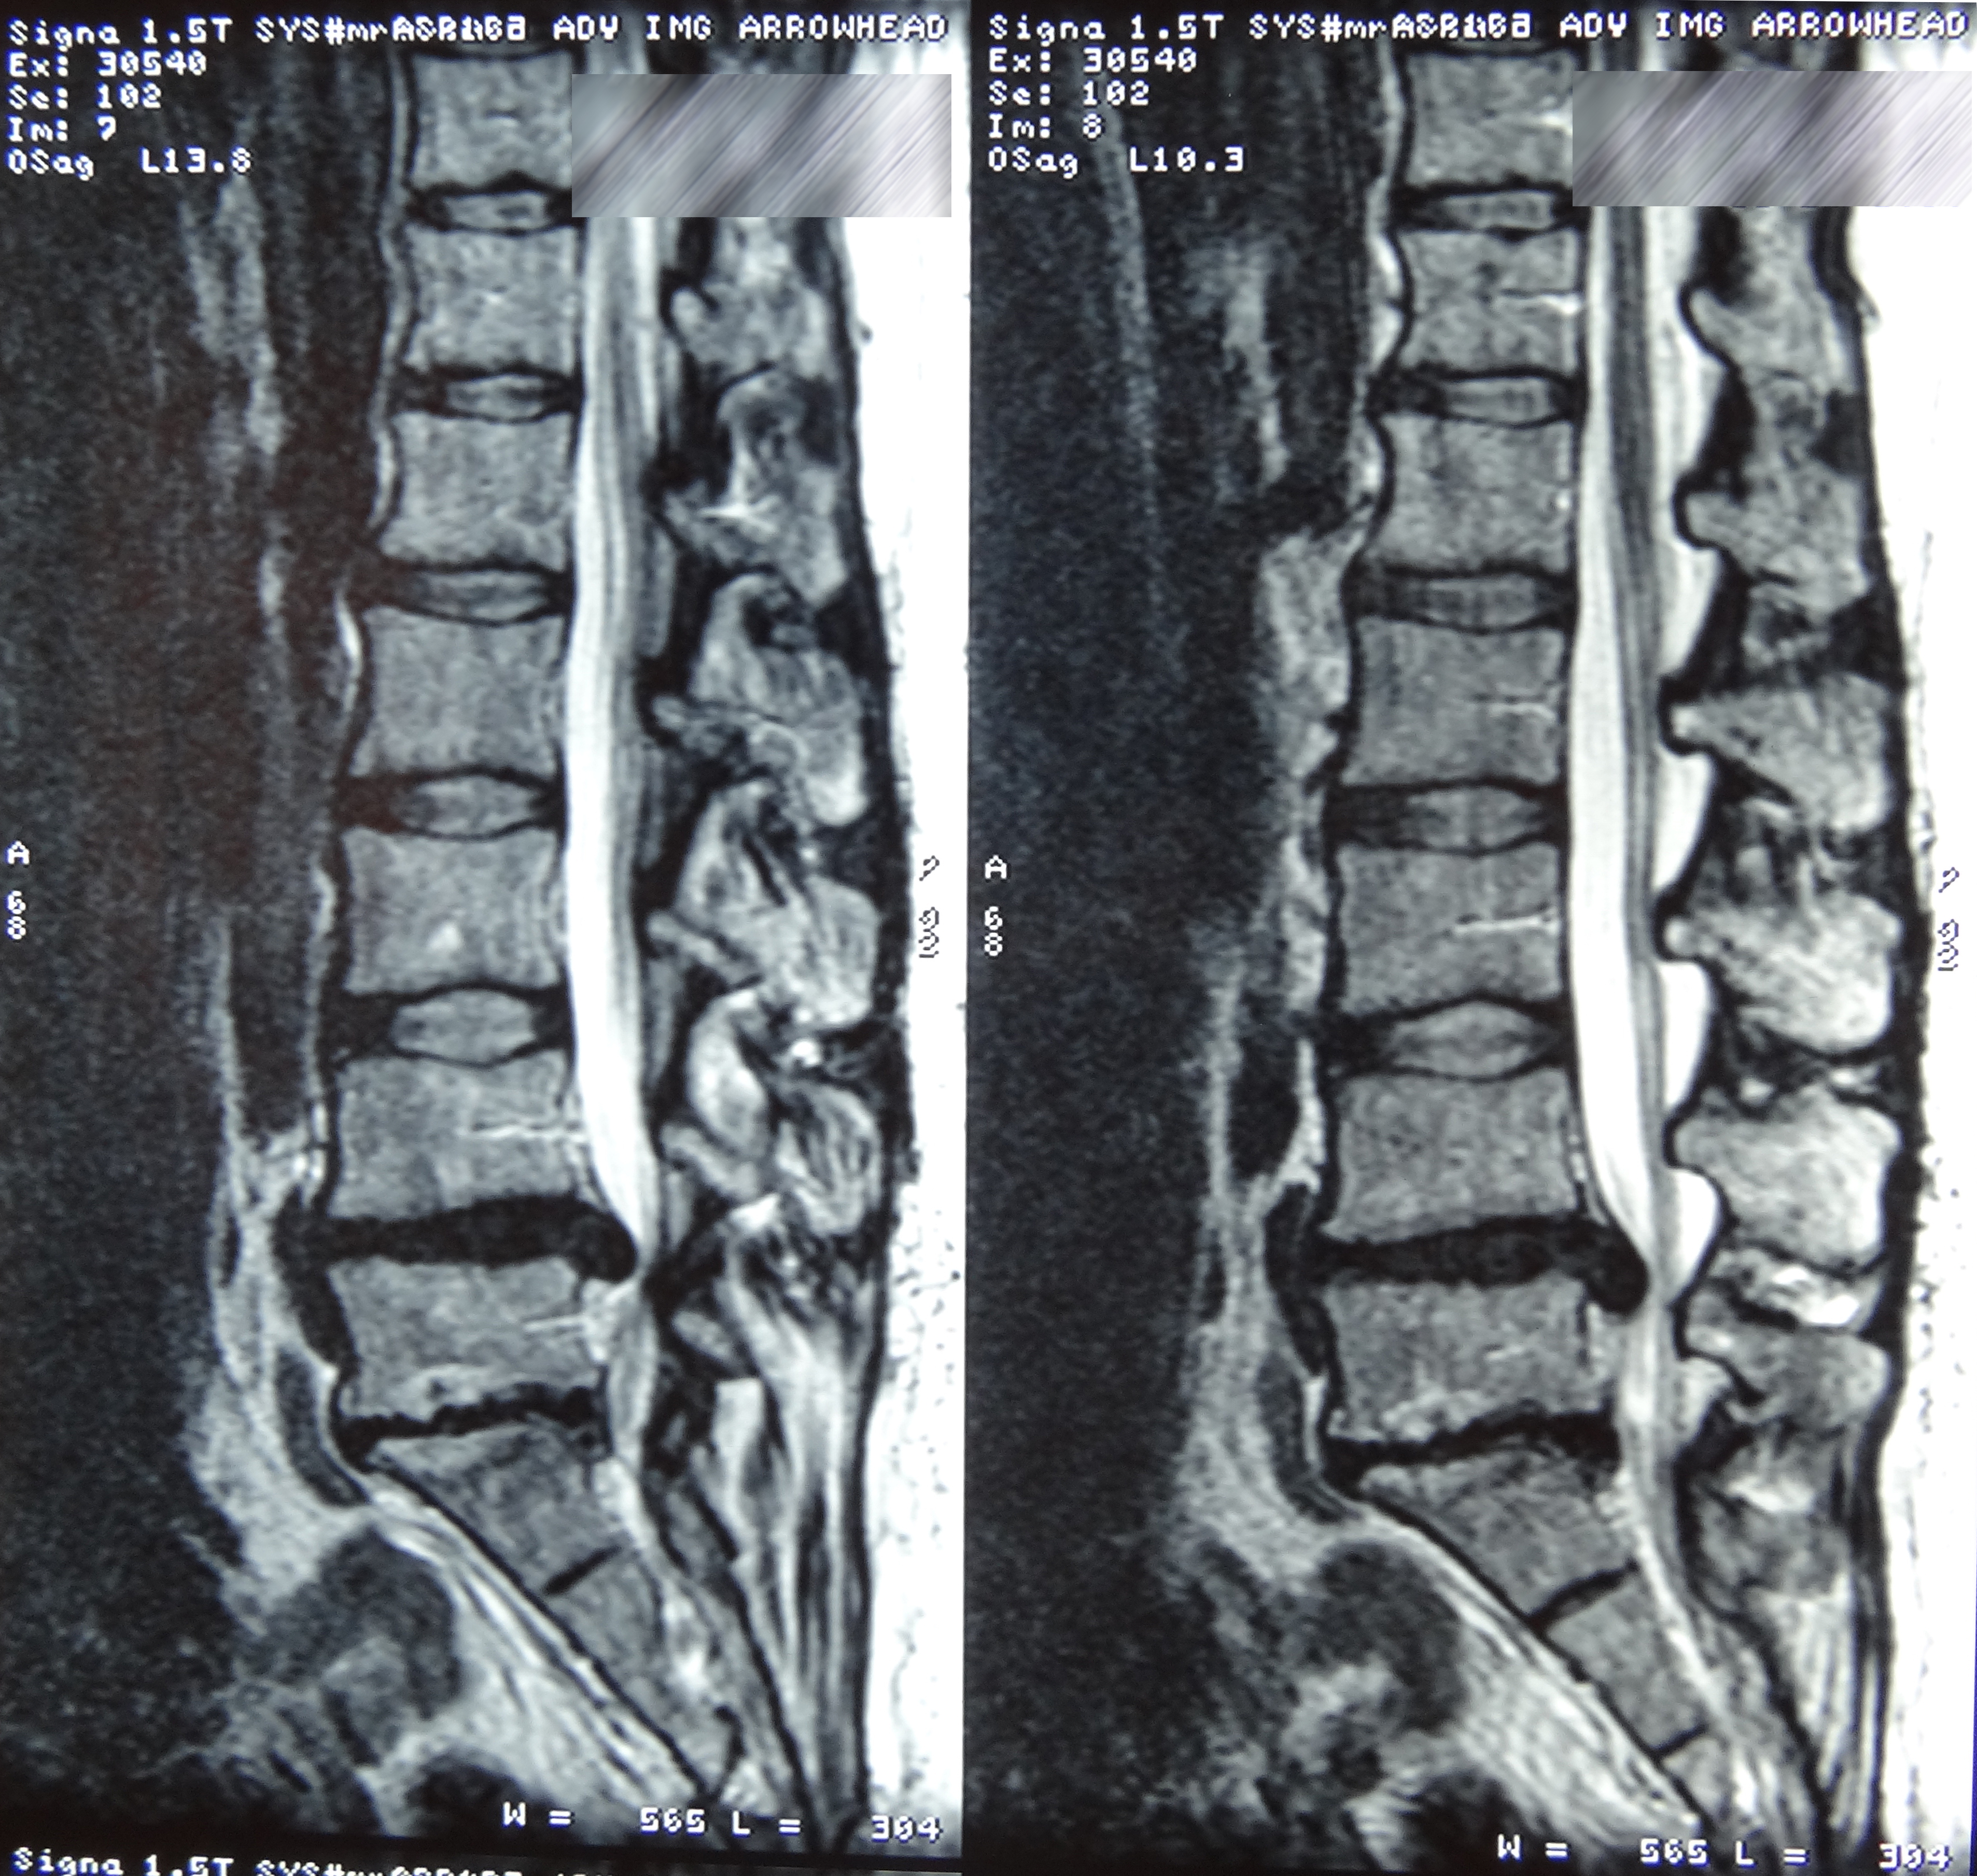

March 2019 MRI

IMPRESSION:

- Complete rupture proximal third anterior cruciate ligament with pivot shift

pattern of bone injuries lateral compartment and contrecoup bone contusion

medial tibial plateau. Joint hemarthrosis. - Complex tear lateral meniscus with inferiorly flipped flap tear extending

into the popliteal hiatus. - Complex tear medial meniscus with outwardly extruded tears of the posterior

horn and body. - Low-grade sprains medial collateral ligament and medial posterior oblique

ligament. - Low-grade sprains fibular collateral ligament and anterolateral ligament.

Intermediate to high-grade sprain popliteofibular ligament and arcuate ligament. - Grade 1 strains vastus lateralis, short head biceps, sartorius, soleus,

popliteus and anterior compartment muscles.

May 2019 MRI

IMPRESSION

- Near full-thickness tear of the anterior cruciate ligament femoral attachment with

associated edema in the intercondylar notch. This is best seen on axial and coronal

images. - Pivot shift bone contusions in a pattern typical of this injury.

- Medial meniscus: Complex tear of the posterior horn of the peripheral third

compromising superior and inferior articular surfaces, with the tear more horizontal

towards the posterior horn/body junction.